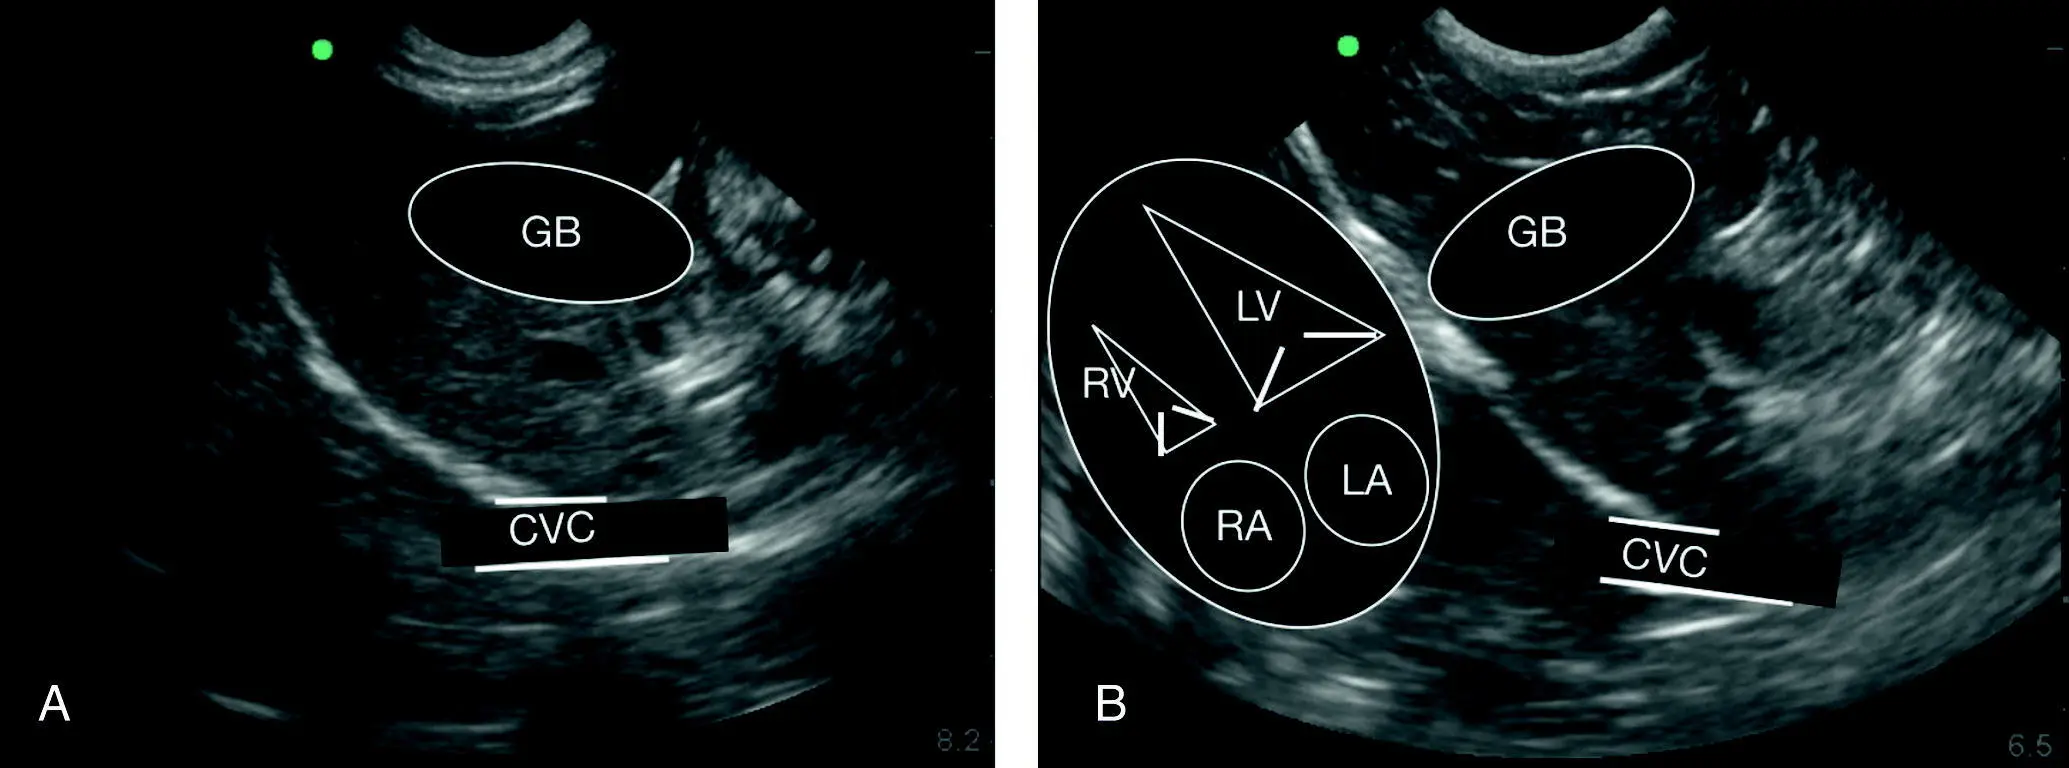

Figure 7.14. Relative positioning of gallbladder to diaphragm to caudal vena cava. (A,B) Line drawing overlays of the gallbladder (GB) and caudal vena cava (CVC). In (A) the heart is faintly visible on the still image analogous to the overlay in (B). In real time the beating heart is readily apparent. (B) Orientation of the heart as it lies against the diaphragm in both dogs and cats. LA, left atrium; LV, left ventricle; RA, right atrium; RV, right ventricle. The orientation and proportionality in the longitudinal plane are nearly identical independent of standing/sternal versus right lateral recumbency.

Source: Reproduced with permission of Dr Gregory Lisciandro, Hill Country Veterinary Specialists and FASTVet.com, Spicewood, TX.